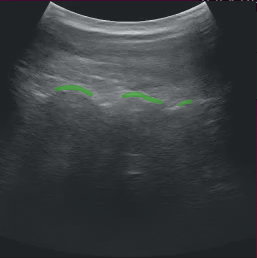

After modifying the application as instructed above, running the application should bring up the ultrasound video with a segmentation mask overlay similar to the image below.

Fig. 11 Ultrasound Segmentation